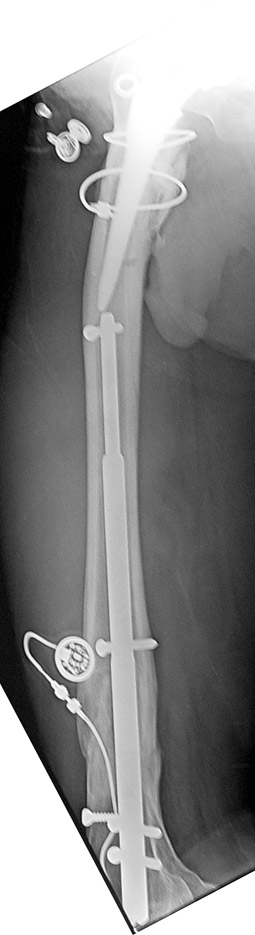

Since 2005 Dr. Mehmet KOCAOGLU is the first most Fitbone operating surgeon in TURKEY. He established the center of excellence for Fitbone surgeries in Istanbul. Fitbone comprises a telescopic nail implant that can extend, powered by an electric motor and controlled by a receiver with an antenna that is buried under the skin; the receiver in turn is controlled by a hand-held radio-frequency transmitter. The procedure for lengthening the lower leg is as follows:

A two-centimetre incision is made at the patient’s knee, and a rimmer is used to create enough space in the bone for a stainless steel nail.

The bone is cut about 14 cm below the knee from the inside with an internal saw. The stainless steel nail is held in place by two screws. The top of the nail is attached to a tiny, plastic-encased receiver that is placed under the skin. The patient controls the lengthening process. By pushing a button on the transmitter when it is placed against the antenna, the built-in motor extends the nail one millimetre per day. When the leg has grown to the desired length, lengthening stops, and the bone is allowed to solidify. The device can be removed about two years after the initial surgery. This procedure, however, comes at a price. While the Ilizarov external fixator costs approximately USD$4,000, and the ISKD implant about USD$8,000, the Fitbone device carries a price tag of roughly USD$15,000 (all prices exclusive of surgery costs).